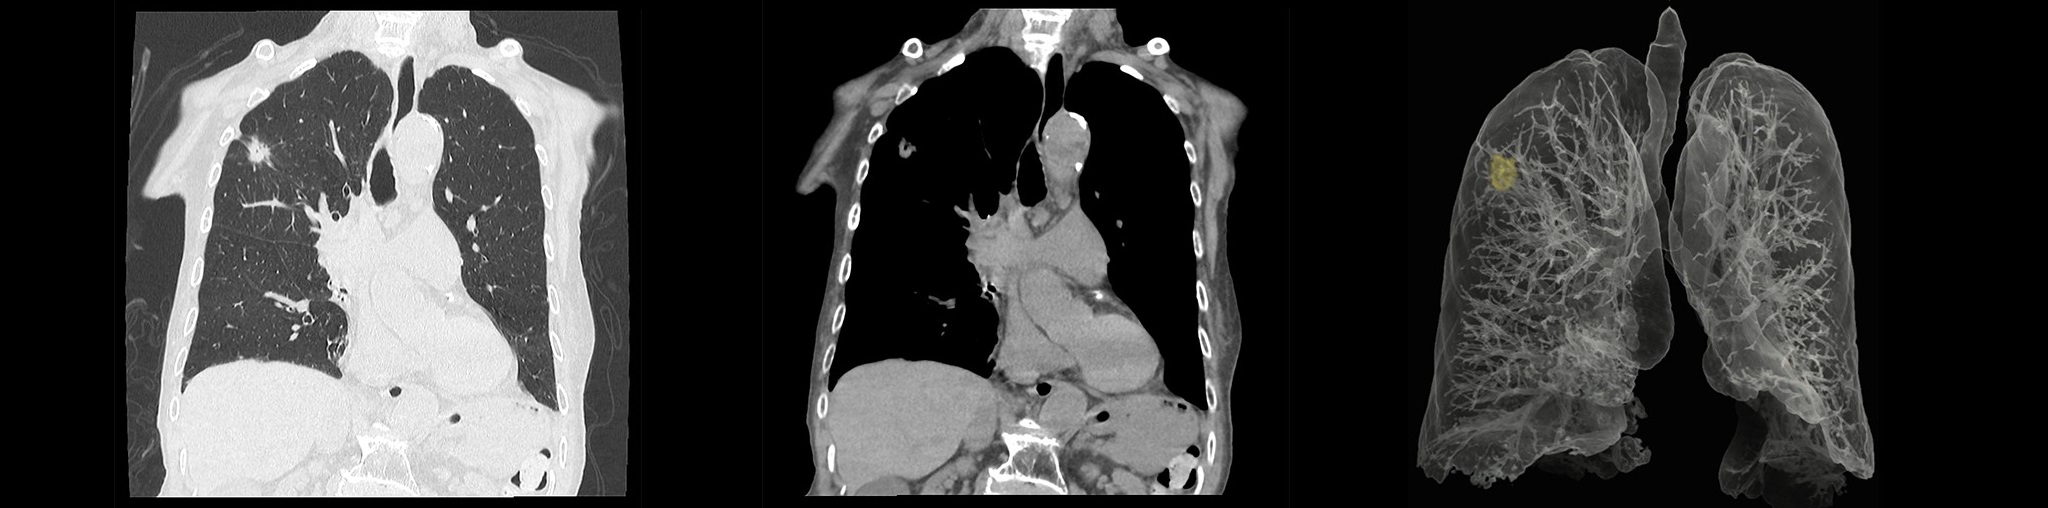

64列マルチスライスCT

最新のマルチスライスCTでより安全な精密検査が受けられます。

従来よりも検査時間が大幅に短縮されました。

2024年3月にCT装置を更新いたしました。

最新の深層学習などの新しいAI技術を採用した、64列128スライスCTスキャナ(富士 フイルムヘルスケア株式会社製「CT装置 Supria Optica」)を導入し、以前よりも短い時間で高画質の撮像が可能になりました。

この検査では、患者様が寝台に横になるだけで、苦痛なく頭部や胸部・腹部の断層像 (輪切り)が鮮明に撮れます。 とくに、らせん状に連続してデータを収集することができ(ヘリカルスキャン)従来の装置より広範囲の検査が行え、 脳出血・脳梗 塞・脳腫瘍・頭部外傷から胸部疾患および腹部臓器(肝・胆・膵・腎・膀胱・その他)疾患にいたるまで、 全身の診断が可能です。

胸部

肺野

CTアンギオグラフィ